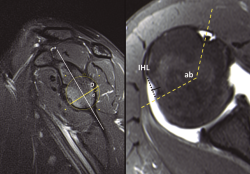

Para realizar la determinación del tracking glenoideo se revisaron las RM preoperatorias de todos los pacientes de acuerdo al método adaptado por Gyftopoulos para su aplicación en resonancia(15). El tamaño de la lesión de Hill-Sachs se estimó mediante la medición del intervalo de Hill-Sachs (IHL)(6) y la medición del ángulo del bíceps modificado (ABM), descrita también por Gyftopoulos(16). El defecto glenoideo se estimó por el método circular modificado: después de determinar el centro de la glenoides, se calcula el diámetro de la glena de acuerdo a un círculo que delimite adecuadamente el borde inferior de la misma. Se calcula el diámetro total y el defecto óseo que quedaría, y se calcula la superficie glenoidea de contacto de acuerdo al algoritmo propuesto por Giacomo(6,15)(Figura 1).

Figura 1. Aplicación de los métodos de medición ósea determinados por Gyftopoulos y cols. Izquierda: determinación del defecto glenoideo mediante el método circular modificado: la línea vertical entre el tubérculo glenoideo y el borde inferior de la glena determina el centro de la misma. D: diámetro total; d: defecto óseo. Para estimar el defecto glenoideo se calcula el algoritmo: Tracking = 0,83D – d. Derecha: Mediciones sobre la cabeza humeral en cortes transversos. El intervalo de Hill-Sachs (IHS) comprende el diámetro anteroposterior del defecto de la cabeza humeral (línea punteada). También se puede estimar la profundidad (línea continua). Ab: ángulo bicipital. Se extiende desde el centro del surco bicipital al borde medial de la lesión de Hill-Sachs.